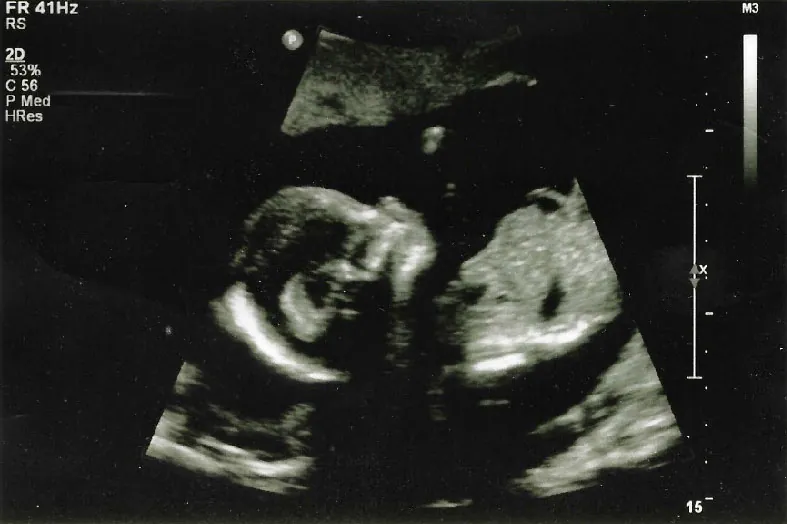

An ultrasound technician will usually perform this test in the clinic. A two-dimensional grayscale abdominal ultrasound is routinely used to evaluate the fetal number, viability, gestational age, anatomic survey, placenta location, amniotic fluid, and maternal pelvic organs (Jabaz & Abed, 2023) (Figure 13.4).

Ultrasound image of fetus in utero during the second trimester.

Figure 13.4 Second Trimester Ultrasound This is a common view expectant parents will have printed that shows the fetusโ€™s profile. The nasal bone, nose, mandible, and hard palate are visible. (credit: โ€œEarly second trimester ultrasoundโ€ by Robyn Alvarez/Flickr, CC BY 4.0)